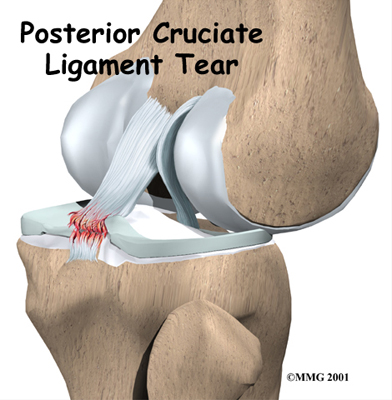

Posterior Cruciate Ligament Injuries

The posterior cruciate ligament (PCL) is one of the less commonly injured ligaments of the knee. Understanding this injury and developing new treatments for it have lagged behind the other cruciate ligament in the knee, the anterior cruciate ligament (ACL), probably because there are far fewer PCL injuries than ACL injuries.